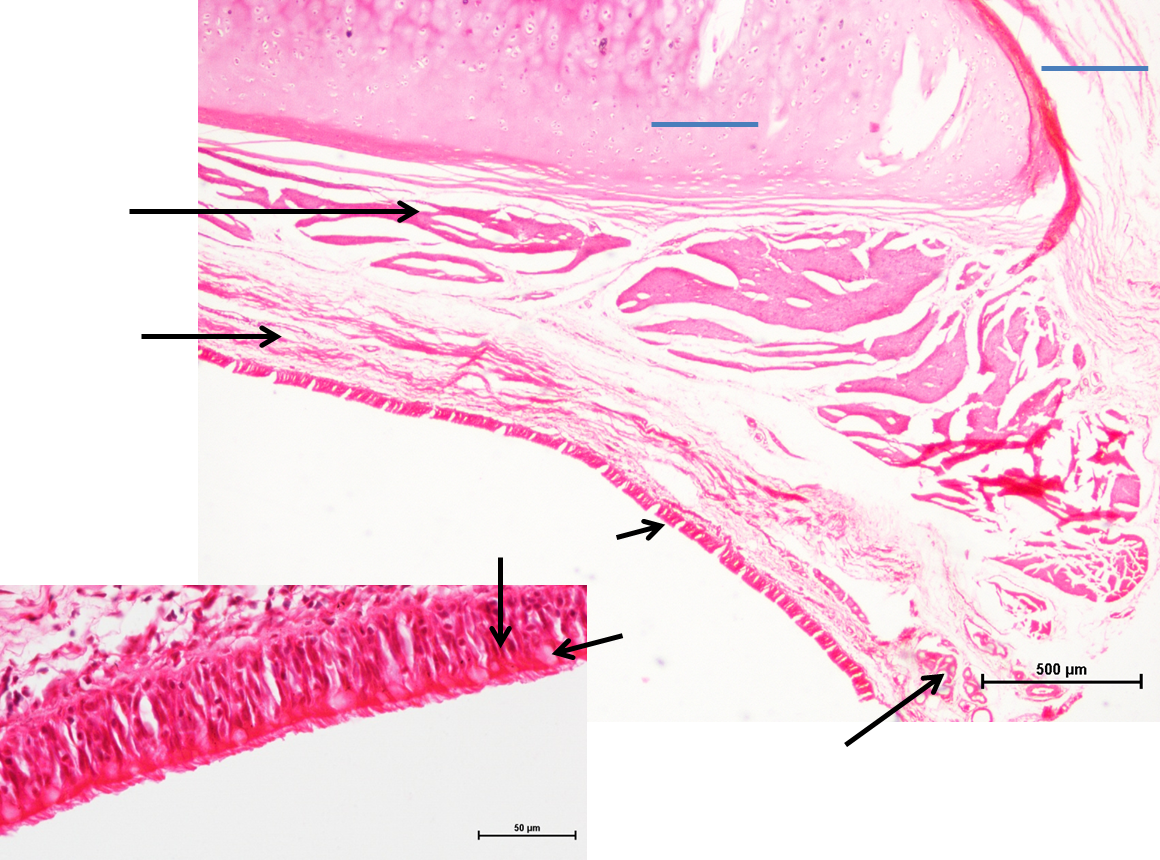

Trachea